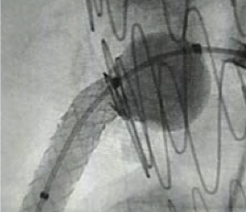

FEVAR

Stent protruding into aorta

Post-dilatation with FLASH

TRUE 360° result